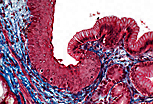

| 光镜下,构成该腺泡的浆液性腺细胞可通过以下特征识别:基底部嗜碱性、细胞核呈圆形且位于细胞基1/3处、顶端区域有嗜酸性的分泌颗粒(酶原颗粒)。 | |

酶原颗粒稳定性较差,在显微制片过程中常难以完整保存。在本图像中,仅能辨认出取样时这些颗粒所处的位置。

圆形的细胞核是区分浆液性腺细胞与黏液性腺细胞的特征。 |

| 在该浆液性腺泡中,细胞顶端可见细胞间小管。这些细胞间小管增大了发生胞吐作用的顶端表面积。 | |

| 浆液性腺细胞合成酶原,其特征为:基底部有高度发达的粗面内质网、圆形细胞核、核上区的高尔基体(该电镜照片中不可见),以及顶端的分泌小泡。粗面内质网的大量存在,是光镜下观察到细胞基底部嗜碱性的原因。 | |